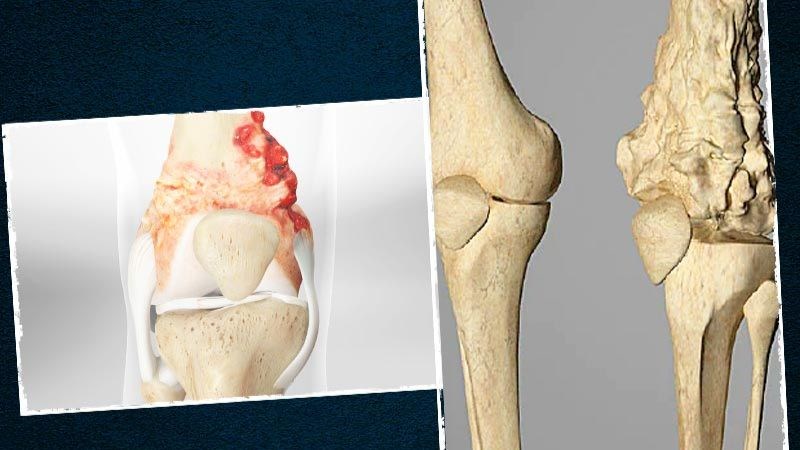

Sarcoma xương (Osteosarcoma)

Sarcoma xương là một loại ung thư xương xuất hiện trong các tế bào hình thành xương. Sarcoma xương thường được tìm thấy ở các xương dài, phổ biến nhất là ở chân, ít gặp hơn là ở cánh tay hoặc ở bất kỳ xương nào trong cơ thể. Trong những trường hợp rất hiếm, nó xảy ra ở cả mô mềm bên ngoài xương.

Độ tuổi thường gặp: Sarcoma xương thường có xu hướng xảy ra ở thanh thiếu niên, nhưng nó cũng có thể xảy ra ở trẻ nhỏ và người lớn tuổi.

Sarcoma xương là một loại ung thư xương xuất hiện trong các tế bào hình thành xương